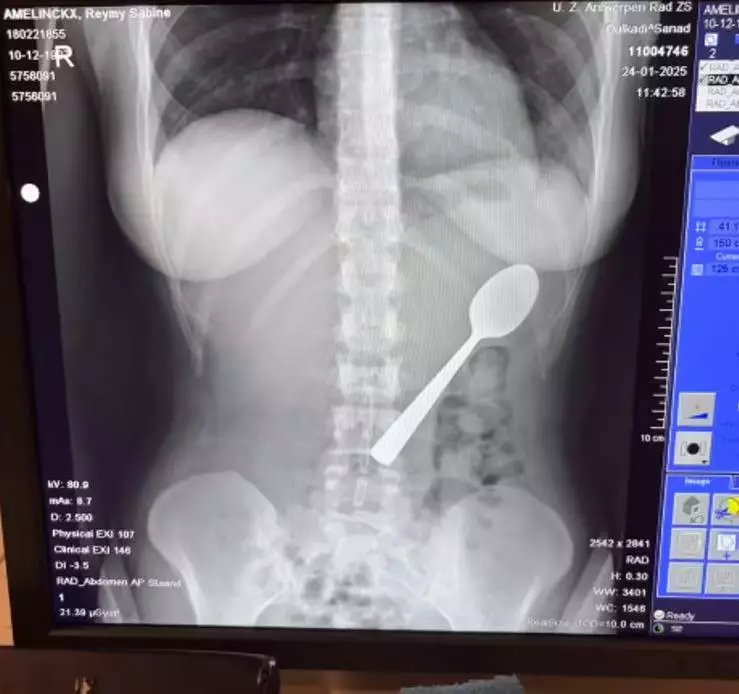

比利時一名女子食乳酪突遭愛犬撲上身,受驚後仰誤吞17CM匙羹入肚,做胃鏡手術終順利取出。

日前,比利時一名28歲女子阿美林克斯(Reymy Amelinckx)坐在梳化上吃乳酪,期間將匙羹暫時含在口中,以騰出雙手回覆訊息。未料,家中飼養的匈牙利維茲拉犬「馬利」(Marley)突然跳上她的雙腿,令她受驚後仰,17CM的匙羹隨即滑入並卡在她的喉嚨內。

嘗試取出無果 女子被迫吞下匙羹

阿美林克斯當下感到驚慌失措,曾嘗試用手將匙羹取出,惟情況並不理想,最終只能在吞下匙羹或出現窒息風險之間作出選擇,最後將匙羹整支吞了下去。她又指,男友回家後自己一度感到尷尬,未有即時道出實情,惟忍耐至晚餐後,身體愈發感到不適,才意識到問題的嚴重性。

匙羹過大需安排胃鏡手術

阿美林克斯之後前往醫院求診,醫生表示該匙羹體積過大,無法經自然途徑排出,只能安排胃鏡手術取出。她在家中等候期間,能清楚感覺到匙羹在體內移動,位置接近肋骨,形容不適感相當明顯。經歷約兩日等待後,醫生在局部麻醉下成功將匙羹取出。由於匙羹尺寸問題,手術過程中需多次調整角度,期間引致少量胃部出血。